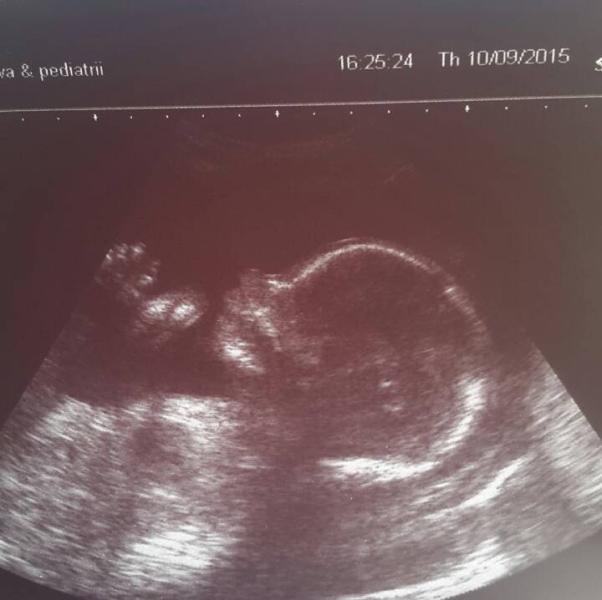

Сегодня нам 22 недели :) ходили на узи в нииап, к Логачеву Валерию Владленовичу! Врач мне понравился, все нам показал (заходила с мужем) Два раза для точности показал нам, что у нас футболист (или боксер, как хочет папа) 😄 В общем, у нас все хорошо, но для врача отметили, низкая плацентация (2,8 см)